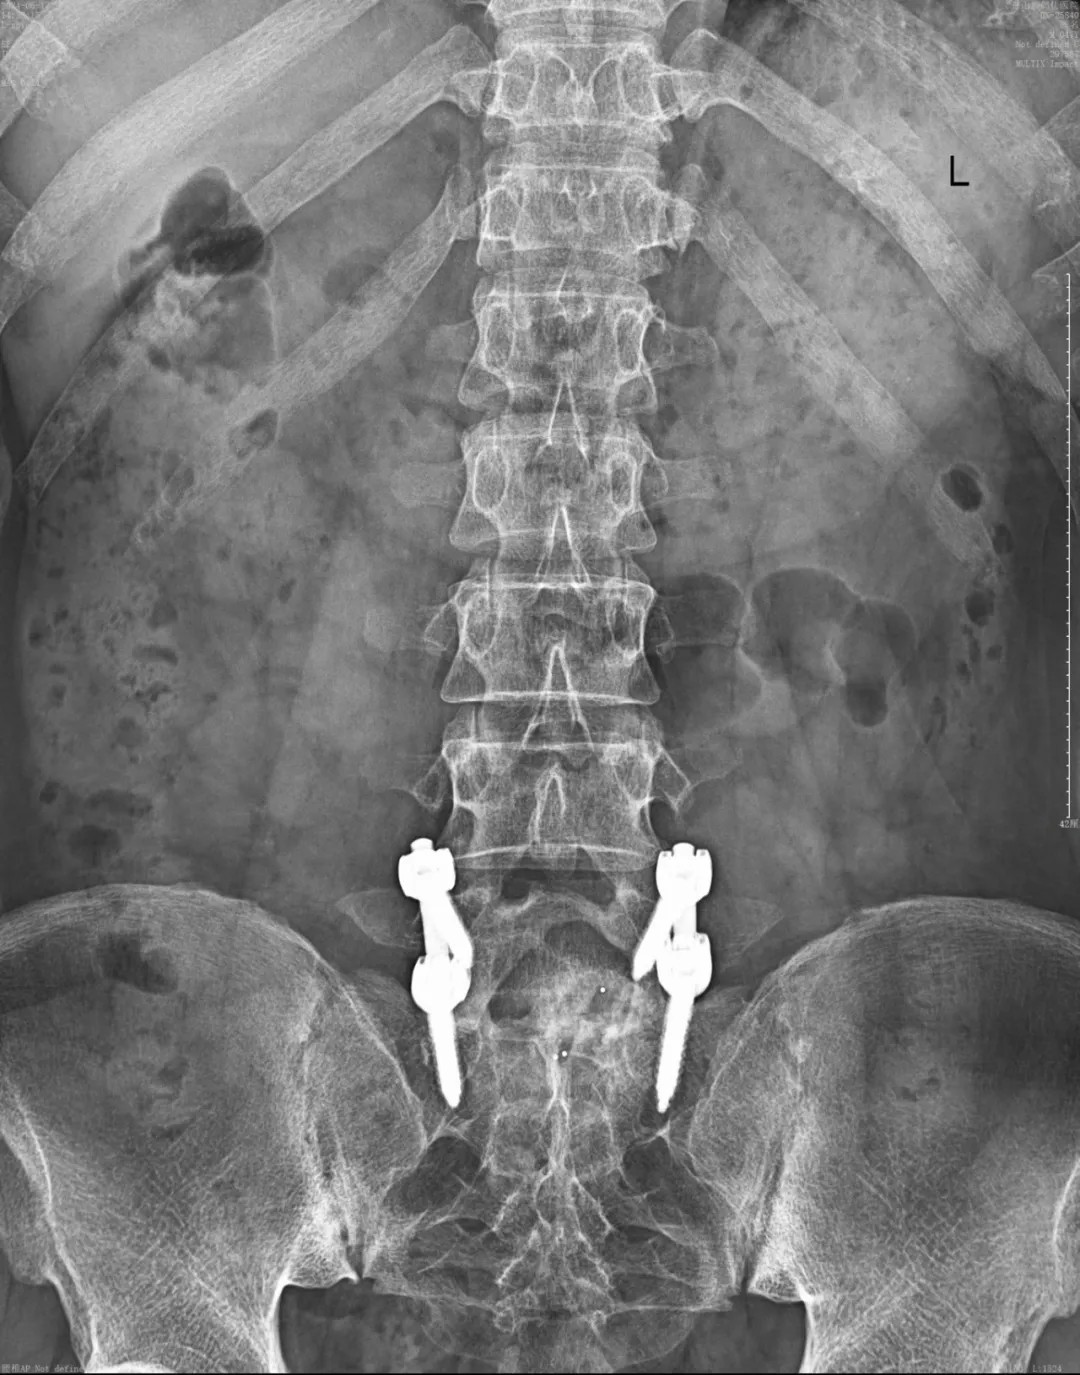

術(shù)后,結(jié)合中藥口服調(diào)理,配合中醫(yī)定向透藥、超聲波等康復(fù)輔助治療。在我院醫(yī)護(hù)團(tuán)隊(duì)的精心護(hù)理下,患者由監(jiān)護(hù)病房轉(zhuǎn)入普通病房,目前已順利出院并來院復(fù)診。

復(fù)診查體顯示切口愈合良好、腰背部肌力較之前明顯恢復(fù)、無下肢放射性疼痛、腰背部轉(zhuǎn)測活動(dòng)較好,雙下肢直腿抬高也明顯改善,整體恢復(fù)良好,定期復(fù)診及注意靜養(yǎng)即可。